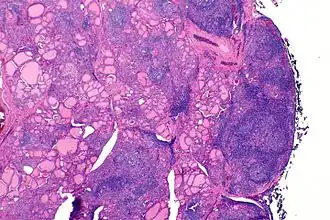

De schildklier van iemand met de ziekte van Hashimoto, zoals gezien door een microscoop